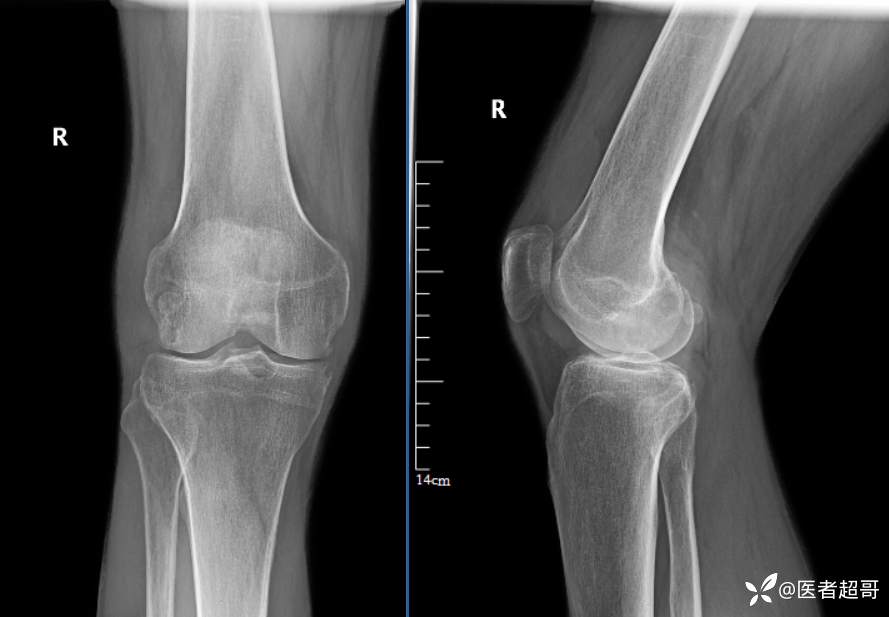

华夏览雄 等 2 位达人已点赞男性,55岁,右膝关节疼痛伴活动困难2年余

两年前外院行右膝包块切除术,术后病理为“肉芽肿”,具体不详,患者术后经常右膝关节积液,右膝活动困难,右膝疼痛明显

实验室检查:白细胞计数:9.0×10^9/L;葡萄糖(空腹):6.93mmol/L↑